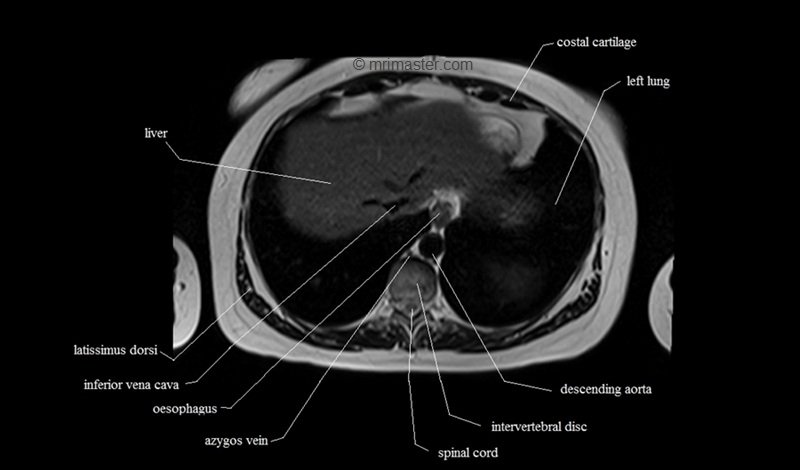

MRI Axial Cross Sectional Anatomy of Chest

This MRI chest (thorax) axial cross sectional anatomy tool is absolutely free to use. Use the mouse scroll wheel to move the images up and down, or alternatively, use the tiny arrows (→) on both sides of the image to navigate through the images. For a more detailed view, double-click the image to view it in full screen, and use the menu in the top right-hand corner to view individual slides or play them in a loop.